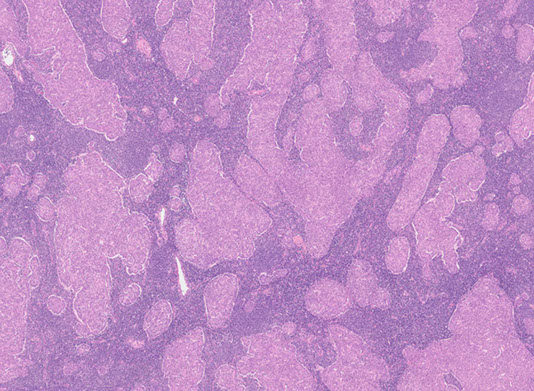

Multinodular thymoma with lymphoid stroma (MNTL)

Rare subtype that accounts for ~1% of all thymomas

- are rarely associated with myasthenia gravis

- vast majority are stage I tumors, and the remaining are minimally invasive (stage II) tumors

Gross: often soft and friable

Micro: characterized by multiple, discrete solid nests or cords of tumor cells surrounded by abundant lymphoid stroma with lymphoid follicles

- germinal centers may be seen

- nests often have bland spindle to ovoid epithelial cells with scant cytoplasm with finely dispersed chromatin and inconspicuous nucleoli

IHC: epithelial cell nests can be highlighted using panK, CK 5/6, CK 19, p63, and PAX8

- unlide type A thymoma, the spindled epithelial cells of MNTL lack aberrant expression of CD20

- MNTL has a higher degree of lymphocytic infiltration than type A thymoma

- the lymphoid stroma of MNTL lacks epithelial cells and is comprised of a mixture of CD20+ B-cells, and mature CD3+/TdT- T-cells

MNTL